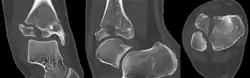

| X-ray of a Tillaux fracture in an 11 year old female | |

A Tillaux fracture is a Salter–Harris type III fracture through the anterolateral aspect of the distal tibial epiphysis.[1] It occurs in older adolescents between the ages of 12 and 15 when the medial epiphysis had closed but before the lateral side has done so,[2] due to an avulsion of the anterior inferior tibiofibular ligament, at the opposite end to a Wagstaffe-Le Fort avulsion fracture